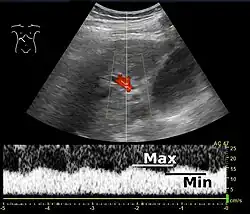

Increased blood pressure in the portal vein, called portal hypertension, is a major complication of liver disease, most commonly cirrhosis.[7] A dilated portal vein (diameter of greater than 13 or 15 mm) is a sign of portal hypertension, with a sensitivity estimated at 12.5% or 40%.[8] On Doppler ultrasonography, the main portal vein (MPV) peak systolic velocity normally ranges between 20 cm/s and 40 cm/s.[9] A slow velocity of <16 cm/s in addition to dilatation in the MPV are diagnostic of portal hypertension.[9]

Portal vein pulsatility can be measured by Doppler ultrasonography. An increased pulsatility may be caused by cirrhosis, as well as increased right atrial pressure (which in turn may be caused by right heart failure or tricuspid regurgitation).[9] Portal vein pulsatility can be quantified by pulsatility indices (PI), where an index above a certain cutoff indicates pathology:

| Index | Calculation | Cutoff |

|---|---|---|

| Average-based | (Max - Min) / Average[9] | 0.5[9] |

| Max-based | (Max - Min) / Max[11] | 0.5[11][12] - 0.54[12] |